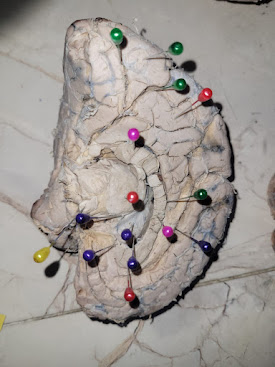

GALERIA DE FOTOGRAFIAS

Realizado el 3 de mayo de 2025.

Actividad desarrollada el SABADO 3 DE MAYO de 2025, agradecer el desprendimiento de los estudiantes de los grupos 3, 5, 9, 12, 16 y 17 de la catedra de Anatomía Humana, que en forma conjunta a sus docentes se realizo el pintado de los cubículos del anfiteatro.